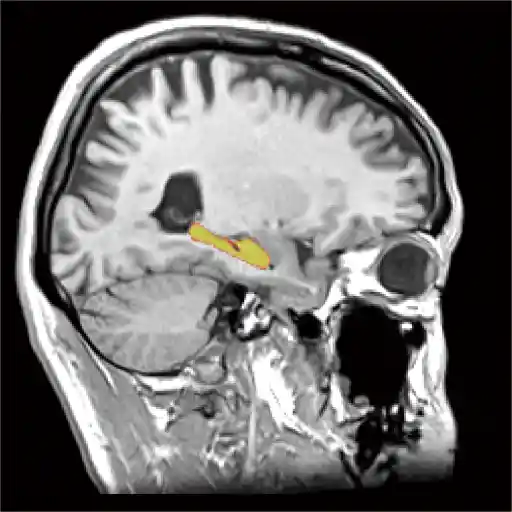

認知症はその前段階である「軽度認知障害(MCI)」を早期に発見することが重要です。血液検査(軽度認知症検査)とMRI画像(VSRAD、海馬の萎縮)を合わせ、MCIを早期に診断しアルツハイマー型認知症を予知・予防します。

7種類のMRI撮影方法を行ない、様々な脳疾患に適切な撮影を行ない詳しく検査します。脳動脈瘤、隠れ脳梗塞、隠れ脳出血、アルツハイマー病 、脳腫瘍などを早期発見し、早期治療へと繋げます。